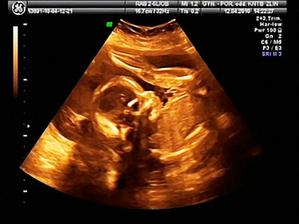

17.2 NT screening - negativní hurá vše je v pořádku prcík měří 7,4cm a je to nejspíš holčička takže naše malá MAGDALÉNKA